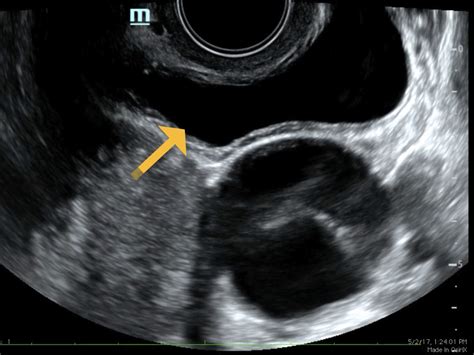

• Transvaginal Ultrasound: In some cases, a transvaginal ultrasound may be performed for a more detailed view of the ovaries. This involves inserting a transducer into the vagina.

• Corpus Luteum: The formation of the corpus luteum after ovulation, which produces progesterone to support the lining of the uterus.

• Ovarian Cysts: Fluid-filled sacs that can be benign or malignant.

• Polycystic Ovary Syndrome (PCOS): A condition characterized by multiple cysts on the ovaries and hormonal imbalances.